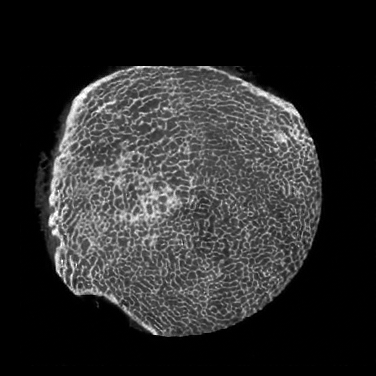

Figure 4: Visual comparsion of SRCT Case 111 from the Tibia dataset. The restored bony structures are shown in the red and yellow boxes in Fig. 5. The display window is [-900, 2000] HU.

Figure 5: Zoomed regions of interest (ROIs) marked by the red rectangle in Fig. 4. The restored image with GAN-CIRCLE reveals subtle structures better than the other variations of the proposed neural network, especially in the marked regions. The display window is [-900, 2000] HU.

III-D Experimental Results with the Tibia Dataset